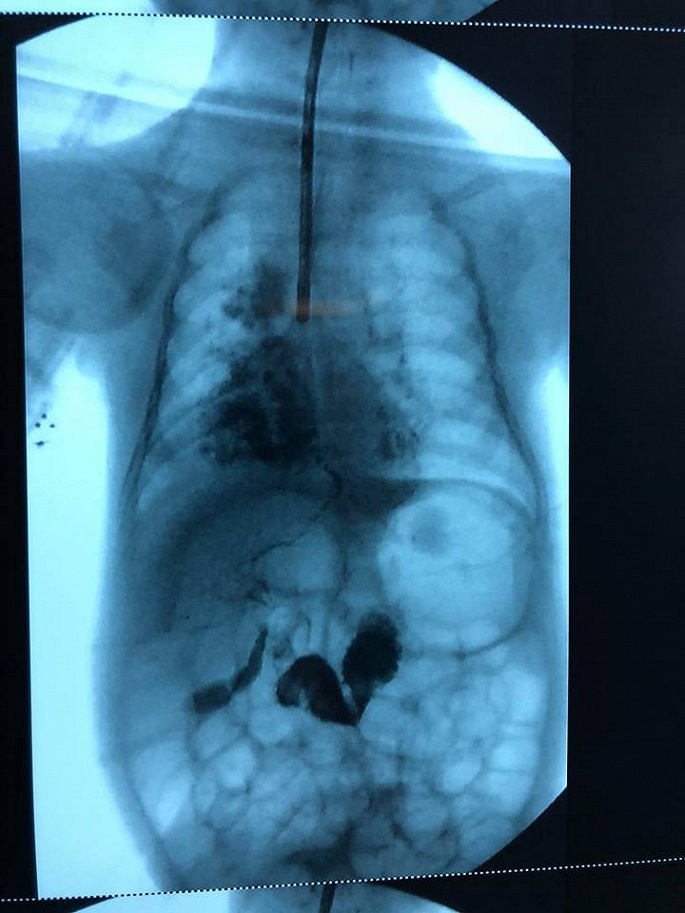

Ảnh chụp phim tình trạng rò khí quản vào đường mật của bệnh nhi.

Hình ảnh nội soi cho thấy mật chảy vào khí quản nơi phân chia hai phế quản trái và phải. Đây là tình trạng khó khăn trong chẩn đoán và rất hiếm gặp, y văn thế giới ghi nhận chưa đến 40 ca riêng lẻ.

Quá trình phẫu thuật, các bác sĩ ghi nhận đường rò khá dài từ gốc carina (nơi chia đôi phế quản trái và phải) xuyên qua cơ hoành đến gan, nằm cạnh bên thực quản và mạch máu, thần kinh vùng ngực.